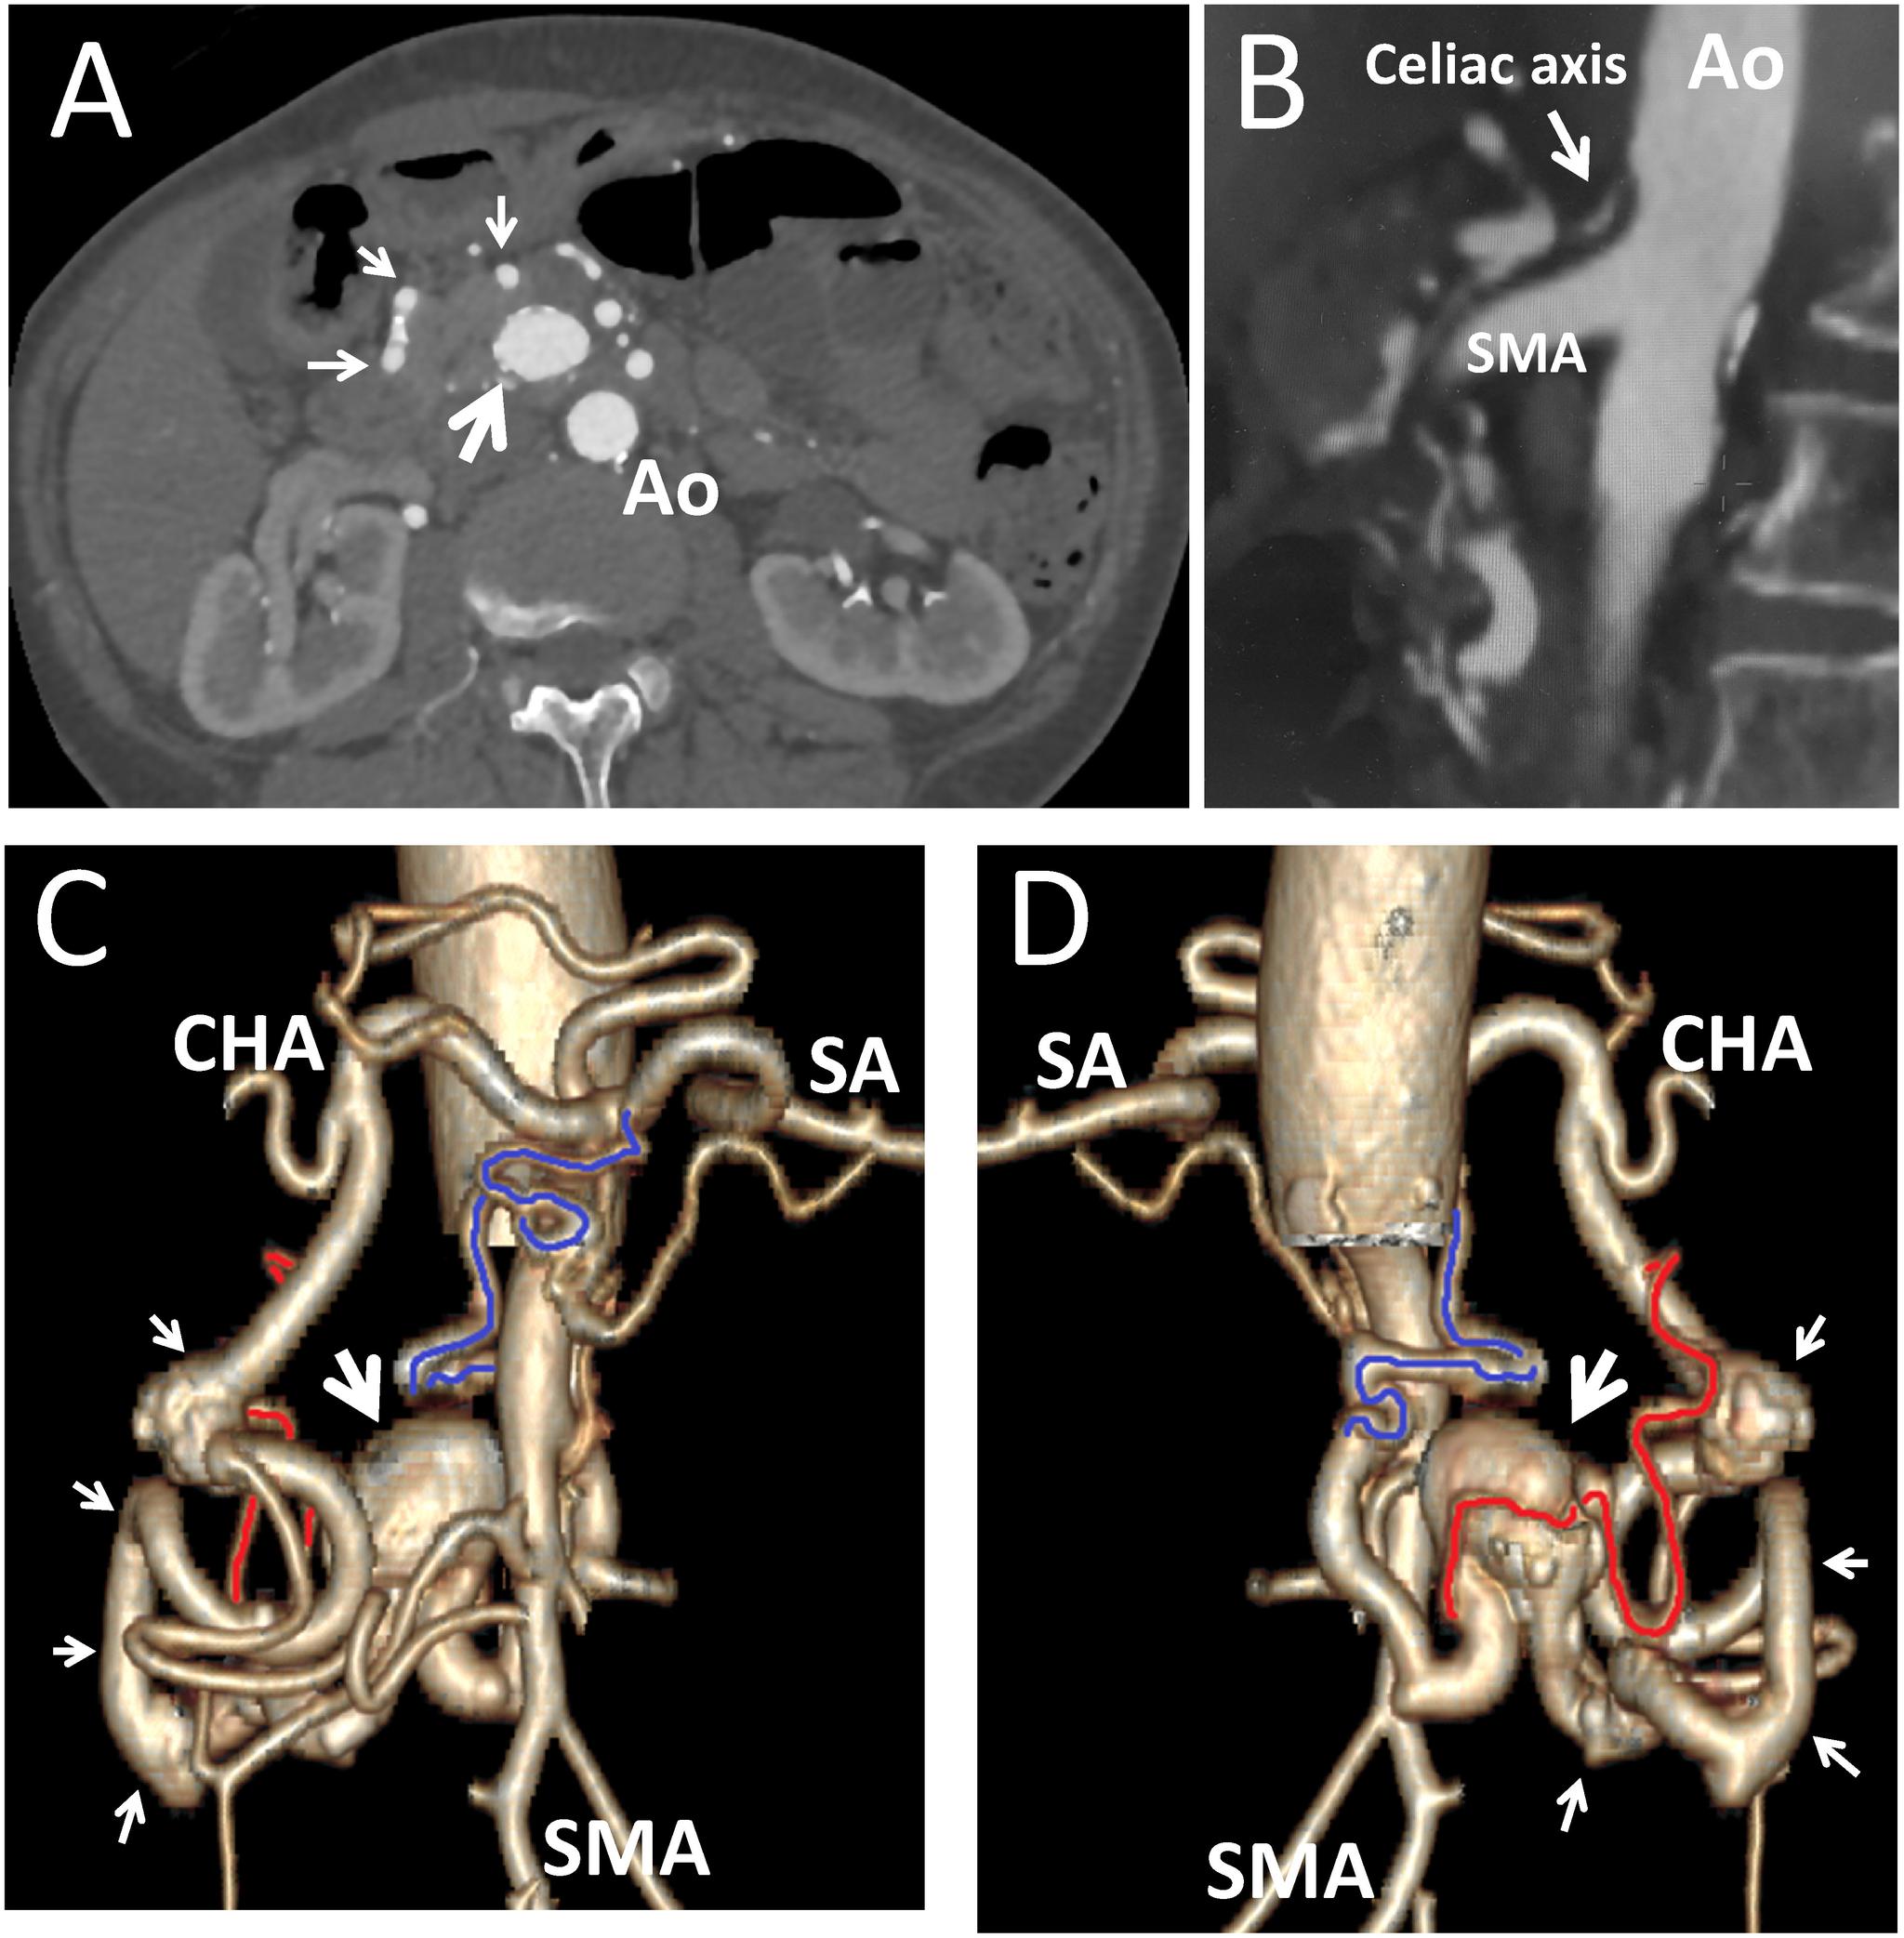

Pancreaticoduodenal artery aneurysm (PDAA) is a rare disease without treatment guidelines. We present two patients with PDAA. The first patient was a 70-year-old man with a pseudoaneurysm in the anterior superior pancreaticoduodenal artery (ASPDA), for which we achieved exclusion by endovascular coil embolization. The second patient was a 63-year-old woman with a PDAA in the ASPDA with celiac axis obstruction. Endovascular coil embolization of the aneurysm and the ASPDA was successful without visceral organ ischemia. Endovascular treatment is effective for PDAAs, but careful evaluation of collateral circulation is vital in PDAAs with celiac axis obstruction.

胰十二指肠动脉动脉瘤(PDAA)是一种罕见疾病,尚无治疗指南。我们报告了两名PDAA患者。首例患者为一名70岁男性,其胰十二指肠上前动脉(ASPDA)存在假性动脉瘤,我们通过血管内弹簧圈栓塞术成功实现了隔绝。第二例患者为一名63岁女性,其ASPDA存在PDAA且伴有腹腔干梗阻。对动脉瘤和ASPDA进行血管内弹簧圈栓塞术成功,未出现内脏器官缺血情况。血管内治疗对PDAA有效,但对于伴有腹腔干梗阻的PDAA,仔细评估侧支循环至关重要。